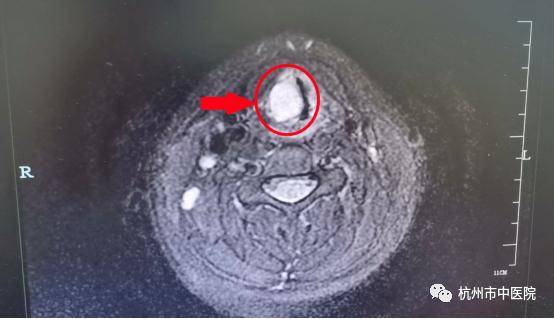

这样一拖就拖到了暑假 , 担心得了大病的媛媛和家人 , 通过亲友们推荐介绍慕名来到我院耳鼻喉科就诊 , 医生们通过完善视频喉镜和喉部增强MR检查 , 初步判断媛媛为喉部肿瘤可能 , 立即将她收住入院行手术准备切除病灶 。

考虑患者年龄较小 , 瘤体的位置紧靠动脉和神经 , 就像一颗“定时炸弹 , 手术风险非常大 , 医生们胆大心细 , 在视频喉镜下精细操作 , 丝毫未损伤周围脏器血管的前提下 , 成功将肿瘤完整切除干净 , 术中几乎没有出血 。

术后经病理科化验 , 媛媛的肿瘤竟然是非常罕见的咽神经鞘瘤 , 万幸手术及时 , 在肿瘤还是良性状态下及时切除 , 成功阻止了一次不小的灾难 , 随着开学临近 , 媛媛的康复状态也一天天好转 , 她兴奋地告诉护士自己的嗓音已经恢复到病发前的八成了 , 过不了多久自己就能变回“甜美小仙女”重返舞台啦!